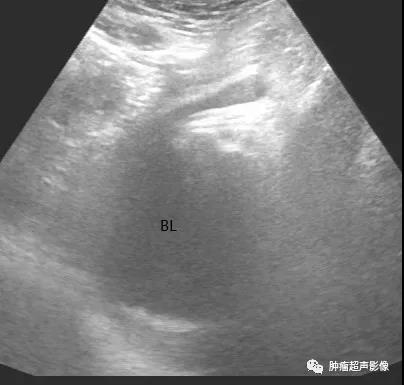

膀胱滑动性疝:超声显示膀胱部分滑入腹股沟,患者尿不尽容易误诊为前列腺问题。